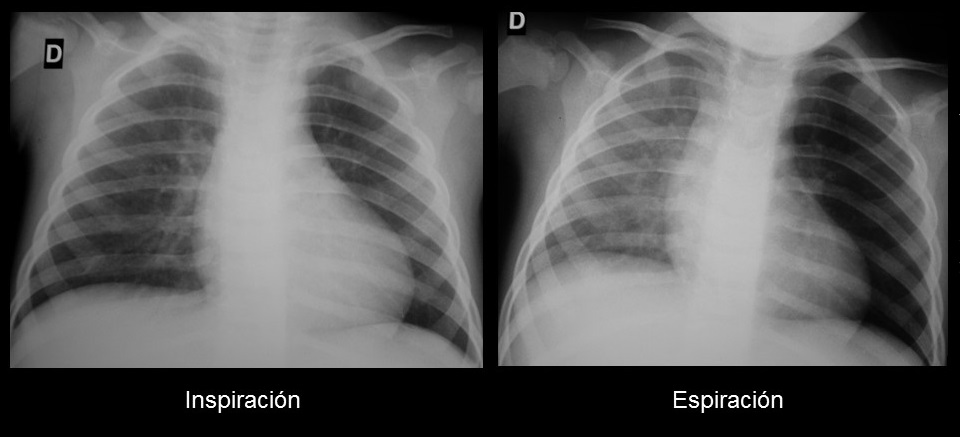

Ante sospecha de cuerpo extraño endobronquial, debemos solicitar radiografías en inspiración y espiración

No es infrecuente que en la radiografía en inspiración no se aprecie ninguna alteración. En la imagen en espiración, apreciaremos hiperclaridad del pulmón afecto por hiperinsuflación, debido a que el cuerpo extraño obstruye parcialmente la vía aérea durante la inspiración, pero completamente durante la espiración. Puede haber desplazamiento mediastínico contralateral y disminución de la vascularización pulmonar. Si se produce una obstrucción bronquial completa, dará lugar a una atelectasia.